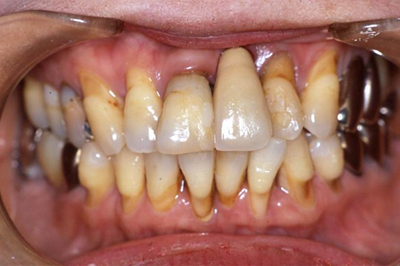

入れ歯の治療例

当院では、患者様が少ないご負担で安心して食事ができるよう、保健治療で入れ歯をお作りしています。同じ入れ歯を10年20年使っていただいている患者様も多くいらっしゃいます。

装着前

装着後